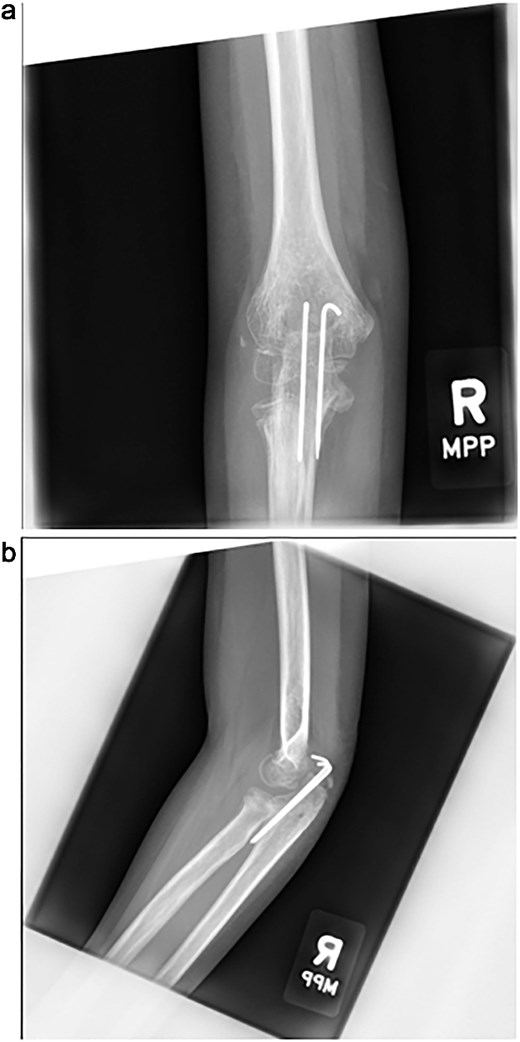

The cast was removed at 5 weeks, and radiographs confirmed maintained alignment (Fig. 4a and b), allowing the patient to transition to a hinged elbow brace. Four months after surgery, she underwent planned removal of the Kirschner wires and tension band (Fig. 5a and b). At 6 months, elbow range of motion was 10°–130° on the right, compared to 0°–140° on the left, and she reported no pain with activities. She was subsequently lost to follow-up.

(a, b) Intraoperative fluoroscopic images following hardware removal at 4 months, demonstrating restoration of joint congruity.